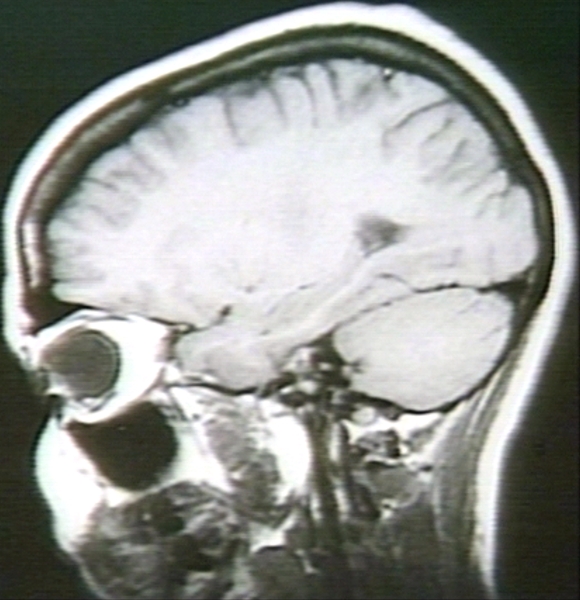

RADIOLOGY: HEAD: HEAD SERIES, SAGITTAL SECTION; BRAIN (MRI)